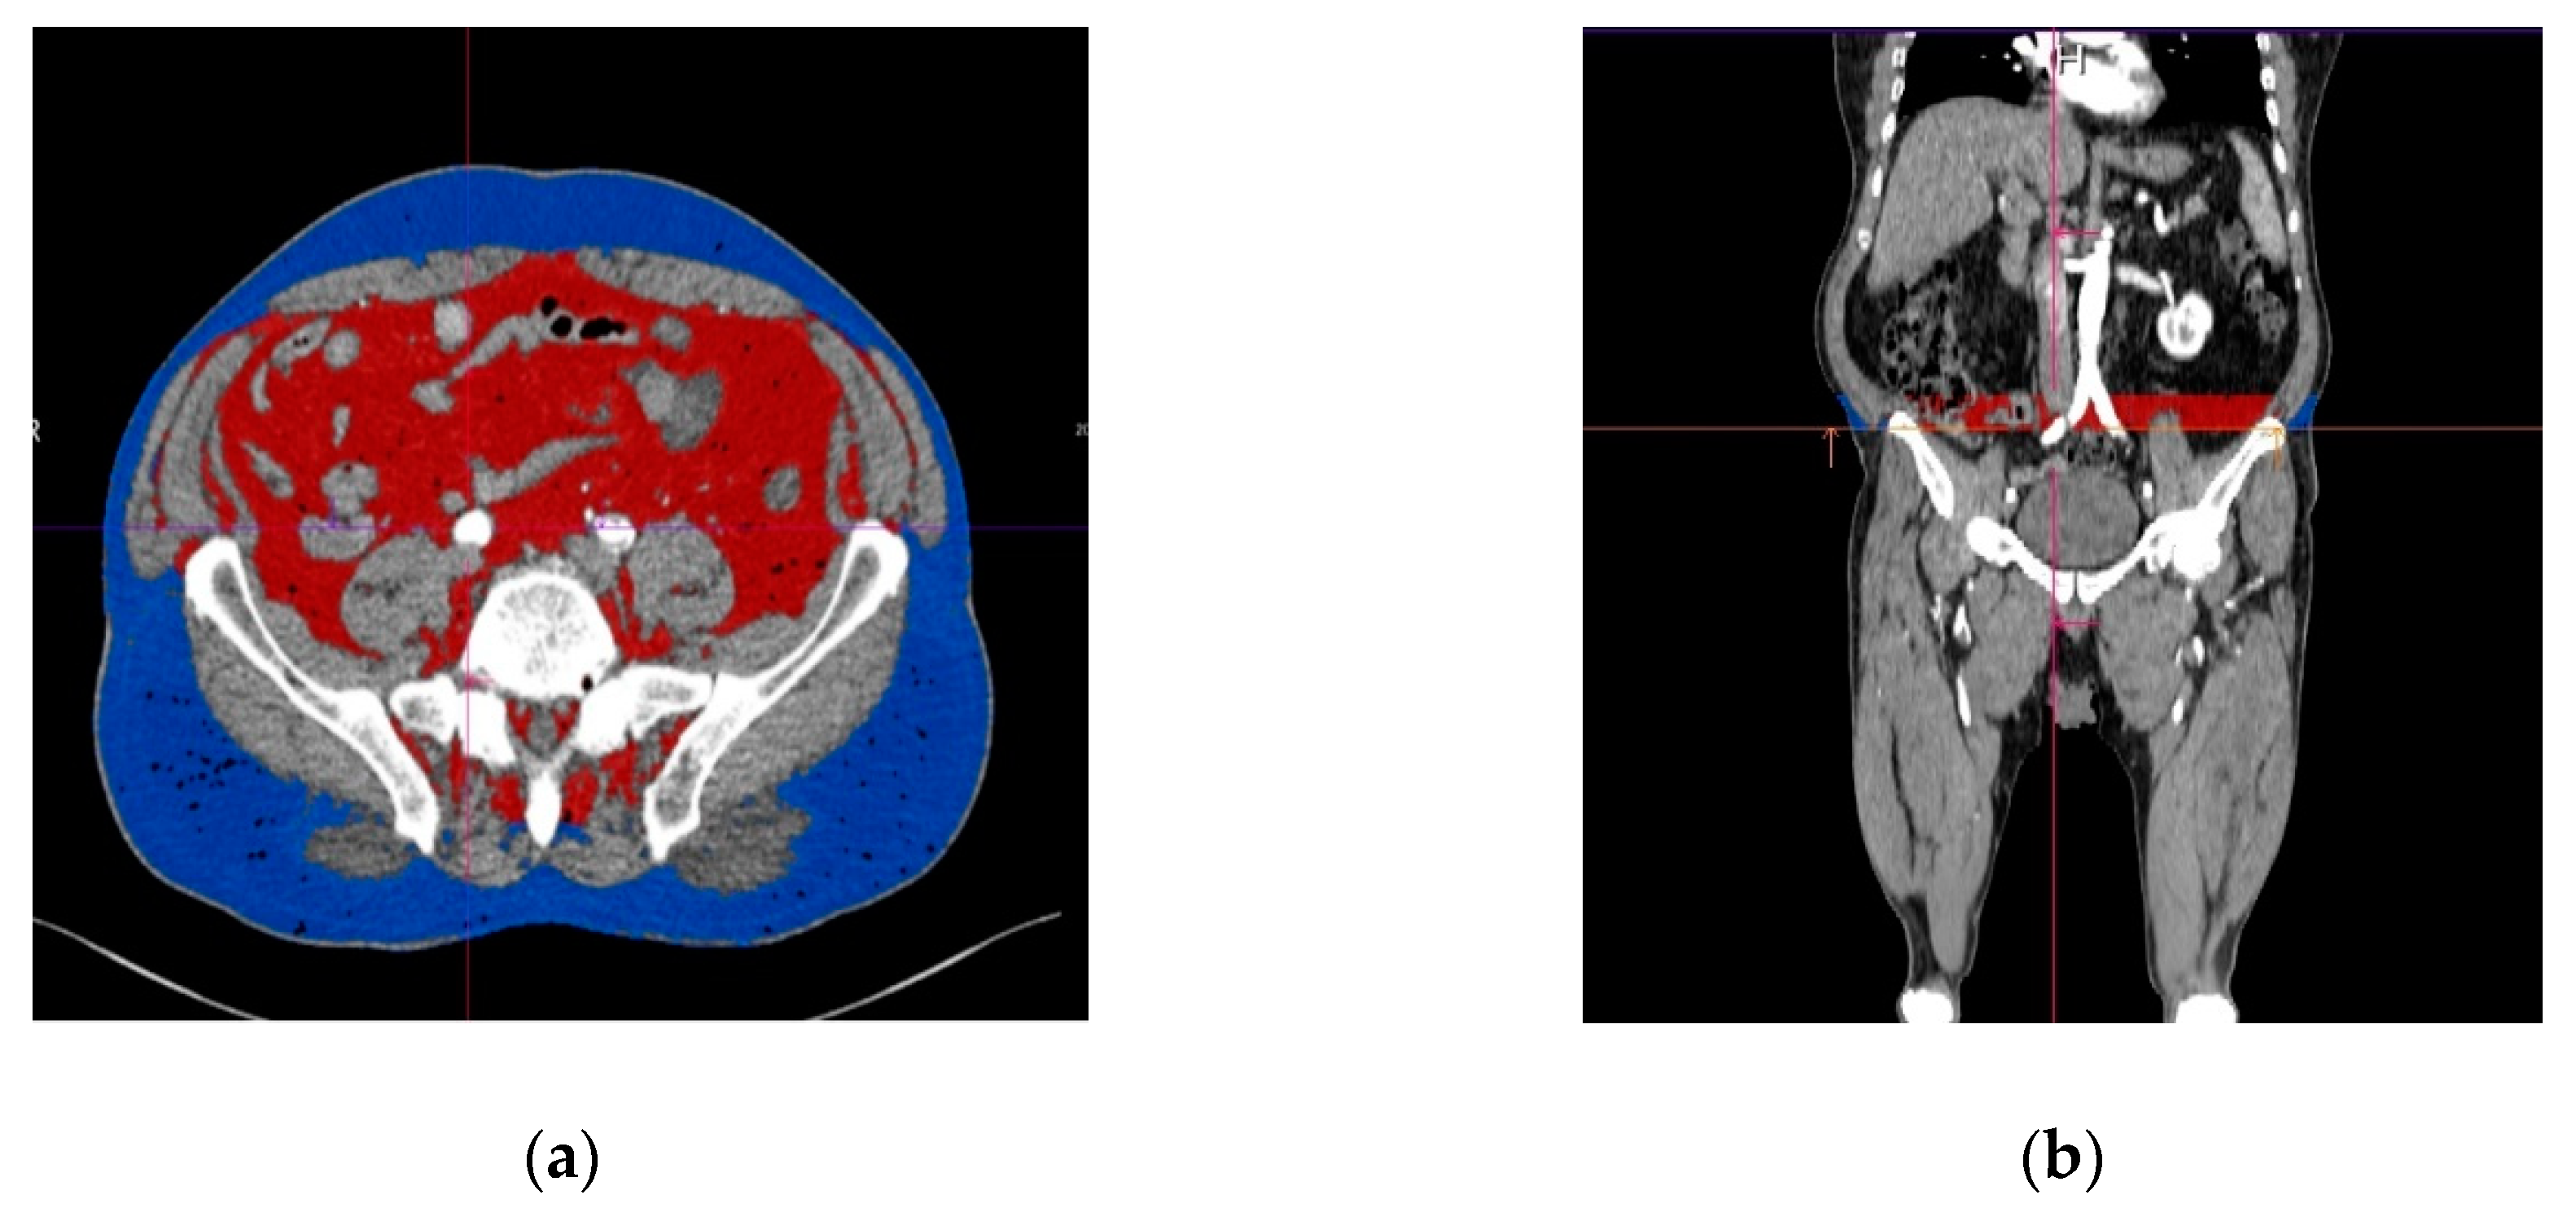

2.2. Computer-Aided CT Image Postprocessing

2.4. Assessment of The Subcutaneous and Visceral Adipose Tissue